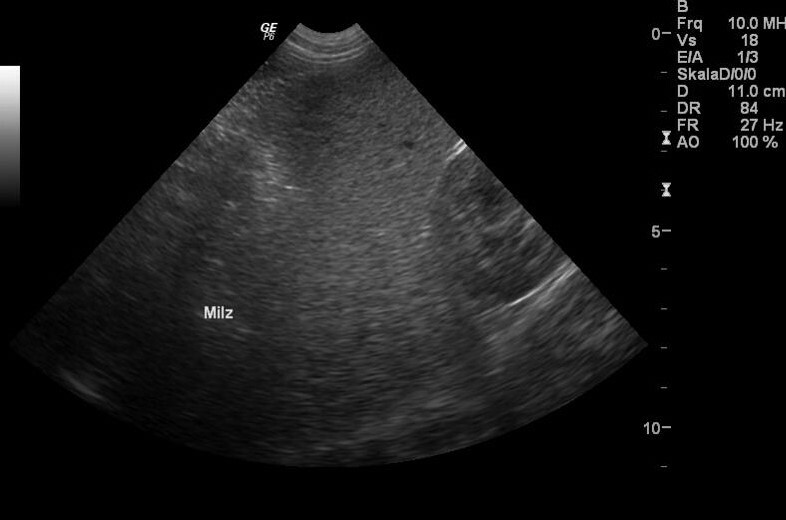

Die Symptome einer akuten Infektion können mild bis hochgradig sein und umfassen Apathie, Fieber, hämolytische Anämie und Thrombopenie. Begleitend können Hämoglobinurie und Ikterus auftreten. Hepatomegalie und Splenomegalie können vorliegen (Abb. 1).